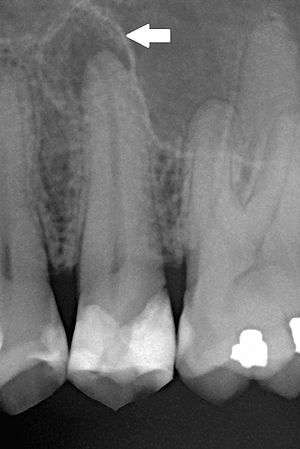

| Periapical dental radiograph showing chronic periapical periodontitis on the root of the left maxillary second premolar. Note large restoration present in the tooth, which will have undergone pulpal necrosis at some point before the development of this lesion. | |

The radiographic features of periapical inflammatory lesions vary depending on the time course of the lesion. Because very early lesions may not show any radiographic changes, diagnosis of these lesions relies solely on the clinical symptoms . More chronic lesions may show lytic (radiolucent) or sclerotic (radiopaque) changes, or both.